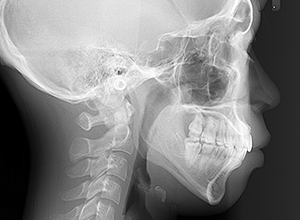

X-Ray

X-Ray所見

セファロ所見 下顎 頭はやや後方に位置しており、下顎枝の長さに対して骨体部は大きく、下顎角は開大しているためハイアングルを呈していた。中顔面部の高さは高く奥行きもあった。前後的にはII級の骨格形態を示していた。